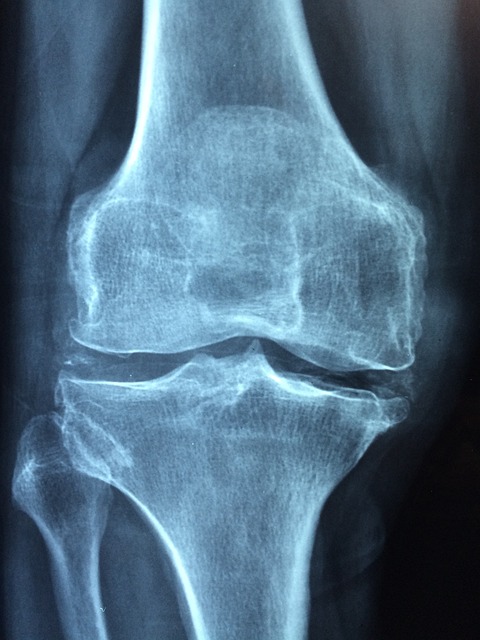

우선 거위발건염의 발병 여부를 확인하기 위해 염증 발생 부위 체크를 위한 엑스레이 및 MRI 검사가 실시됩니다. 결과에 따라 진단이 내려지면 원인에 따라 적절한 조치가 취해집니다. 만약 감염이 원인인 경우 항생제 및 배농술 같은 조치가 취해집니다. 하지만 비감염성인 경우에는 나쁜 생활 습관을 개선하고, 소염진통제, 스테로이드 등을 사용하여 보존적인 치료가 시행됩니다. 이렇게 치료를 받았는데도 불구하고 개선이 없는 경우 점액낭을 제거하는 수술을 고려할 수 있습니다.